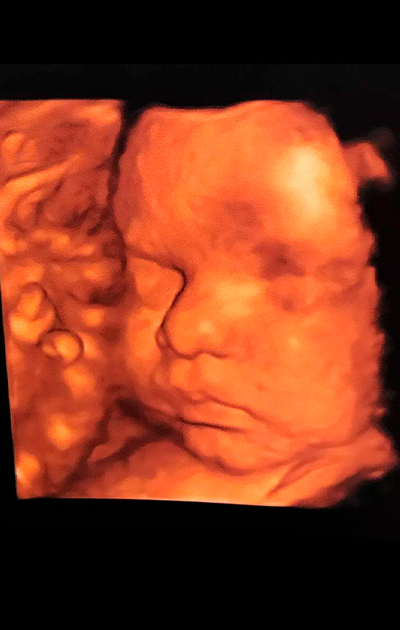

Ultrassons 3D ou 4D

Os ultrassons 3D ou 4D podem ser feitos durante o pré-natal de preferência entre as semanas 26 e 30 e são utilizados para ver detalhes físicos do bebê. O exame em 3D mostra detalhes do corpo do bebê, sendo possível ver o rosto e os órgãos genitais com mais nitidez, enquanto no exame em 4D, além das feições, também é possível visualizar os movimentos do feto na barriga da mãe em tempo real.